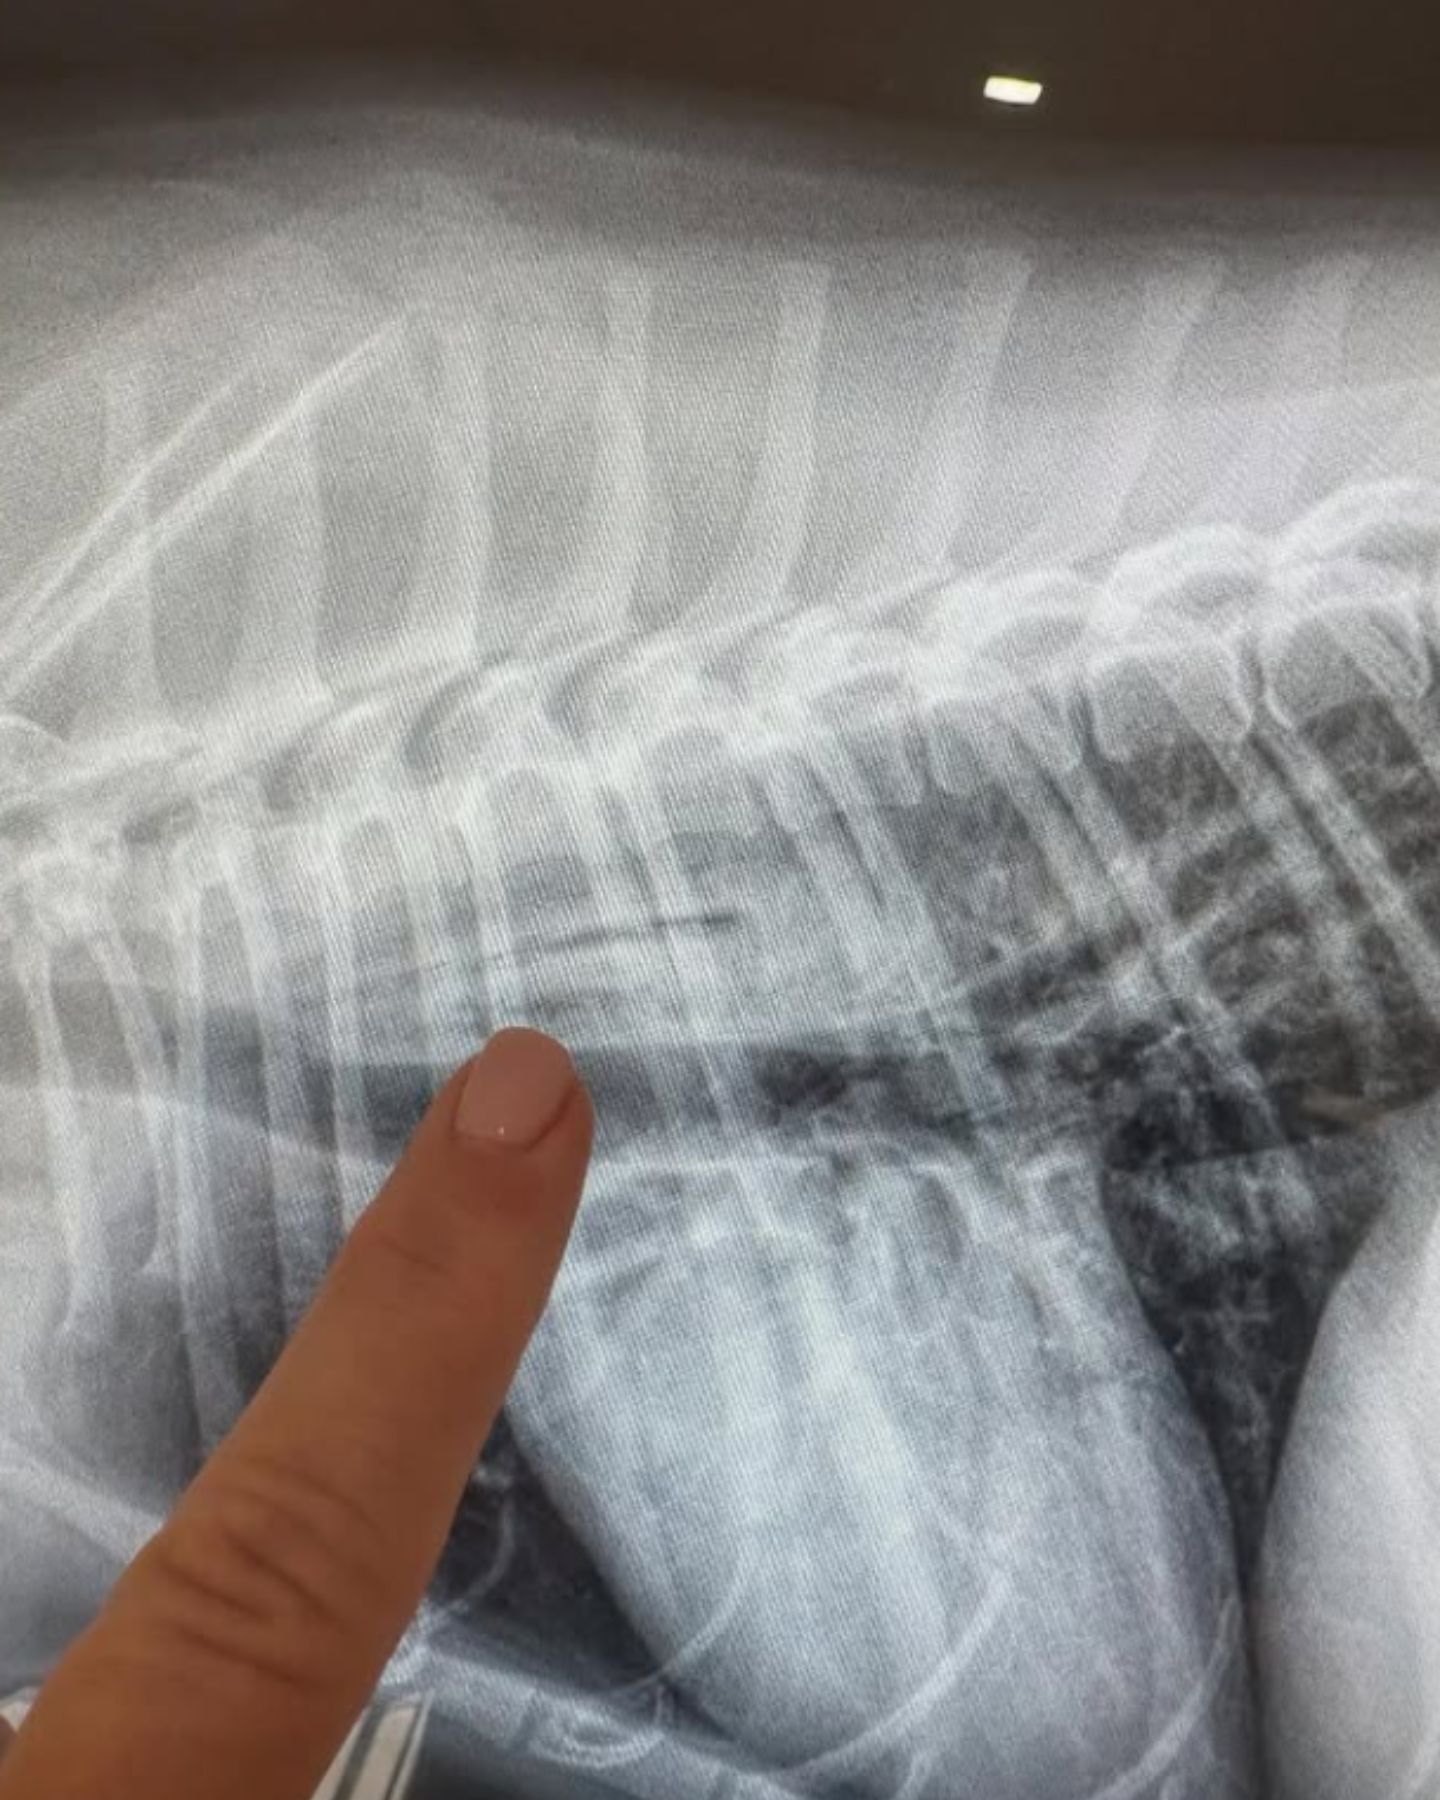

X-rays hinted at something deeper, yet there were no clear answers.

She thought Luna might have gotten to one of the fruits. But scans didn’t show a seed in her belly or throat. The mystery deepened.

It wasn’t until a special barium study was ordered that the truth finally appeared. The seed had been stuck in Luna’s throat the whole time, almost invisible, yet causing excruciating pain.